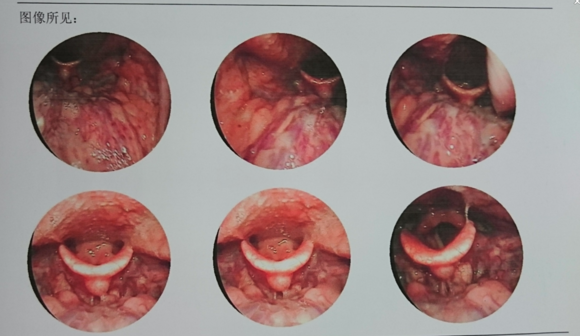

仁品医院的王其峰主任为何先生检查,经德国WOLF内窥镜显示下,他的喉部黏膜慢性充血,喉腔内粘性分泌物较多,会厌舌面可见兜状隆起,表面光滑呈淡粉色,“是典型的慢性咽炎表现”王其峰主任说道。

配图:德国WOLF内窥镜示图